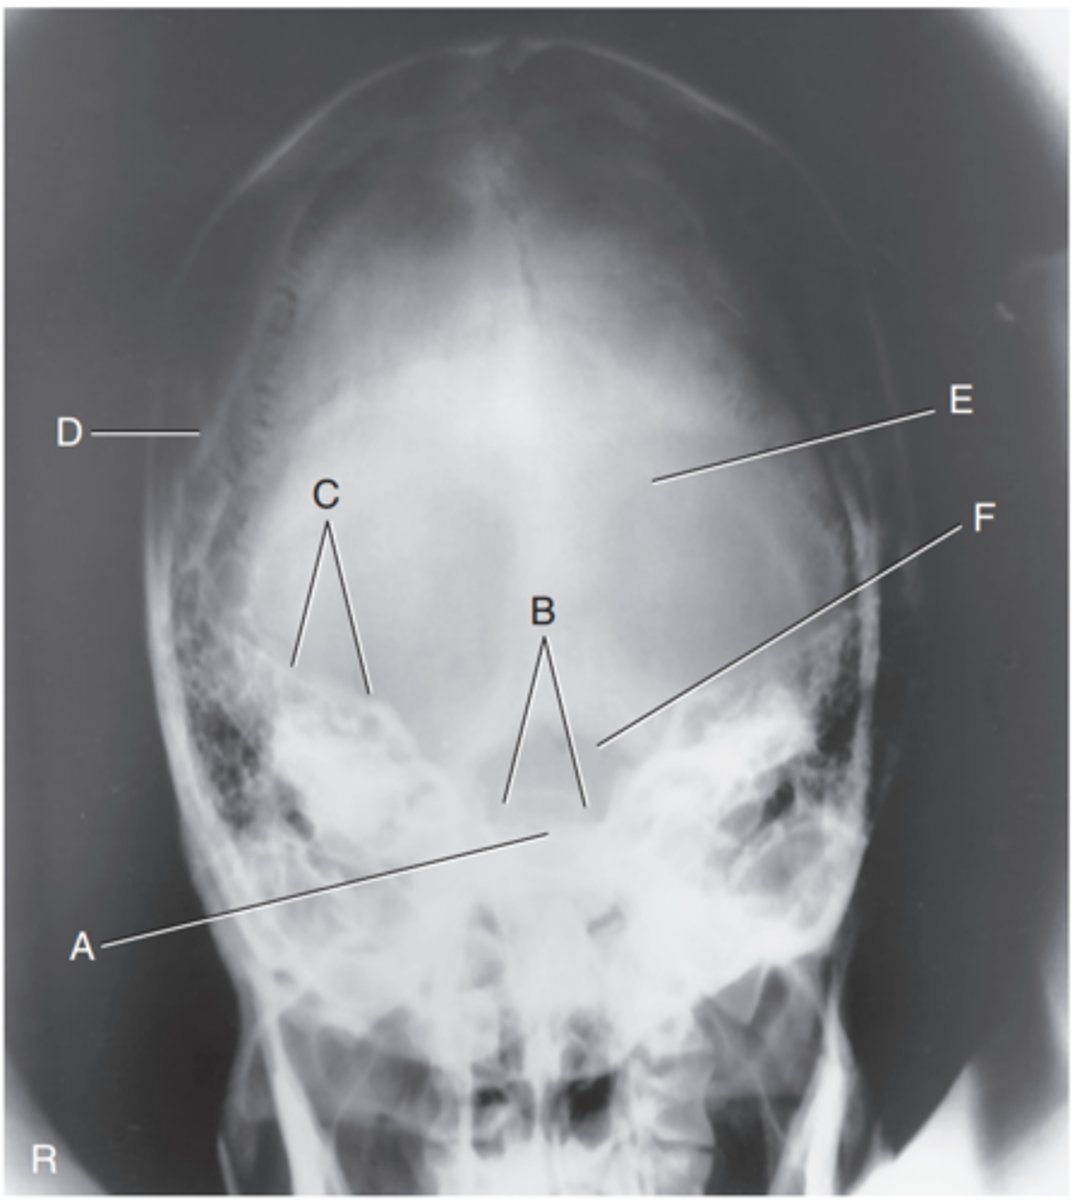

Supraorbital margin of right orbit

Label A

Crista galli of ethmoid

Label B

Sagittal suture

Label C

Lambdoidal suture

Label D

Petrous ridge

Label E